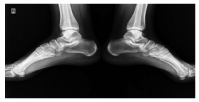

Enthesopathy is a reported side effect of isotretinoin and usually develops after long-term isotretinoin use.[37,38] However, cases associated with short-term isotretinoin treatment have also been reported in the literature. Tendinitis of the Achilles tendon is a known side effect of isotretinoin and has been reported in 9.5% of patients.4 A close relationship between Achilles tendinitis and isotretinoin dose has also been described.[39,40] In our study, the patient who developed tendinitis was on low-dose isotretinoin treatment. Dose reduction and interruption can be considered in patients developing tendinitis.[39] The symptoms of the patient in the current study regressed with the cessation of treatment.